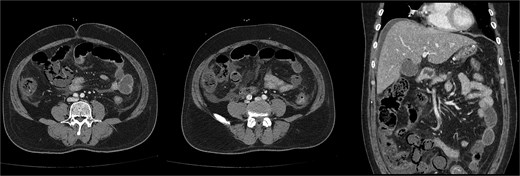

On the first day of ICU admission, the patient received 2000 ml crystalloid fluid and 1300 ml bicarbonate mix fluid. Total fluid input was 5583 ml, and output was 720 ml. Blood glucose was managed by continuous insulin infusion with intermittent bolus administration. The patient was treated with ceftriaxone and metronidazole for suspected bowel ischaemia. ABGA revealed the following: pH 7.36, PCO₂ 18.7 mmHg, PO₂ 85.9 mmHg, HCO₃− 10.4 mmol/l, lactate 6.9 mmol/l, and glucose 423 mg/dl. As hourly urine output remained below 0.5 ml/kg, continuous renal replacement therapy (CRRT) was initiated to resolve volume overload. Dynamic liver CT confirmed diffuse fatty liver, significant thickening, and decreased enhancement of walls in the distal SB and ascending colon, supporting SBI diagnosis (Fig. 2).

Follow-up dynamic liver CT revealed decreased wall enhancement, mural air densities in the distal small bowel and ascending colon compared to the previous noncontrast abdominopelvic CT.